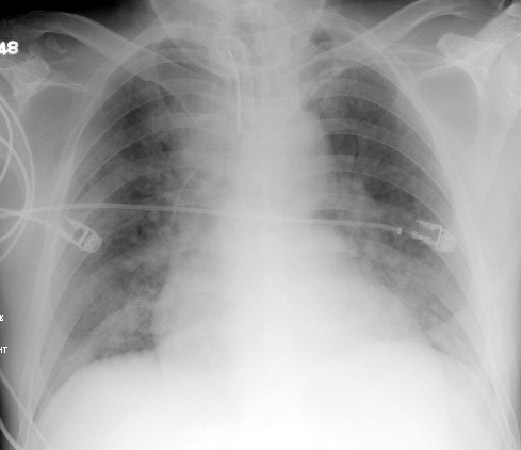

CXR for case found here:

(CXR source: https://www.med-ed.virginia.edu/courses/rad/cxr/pathology2chest.html)